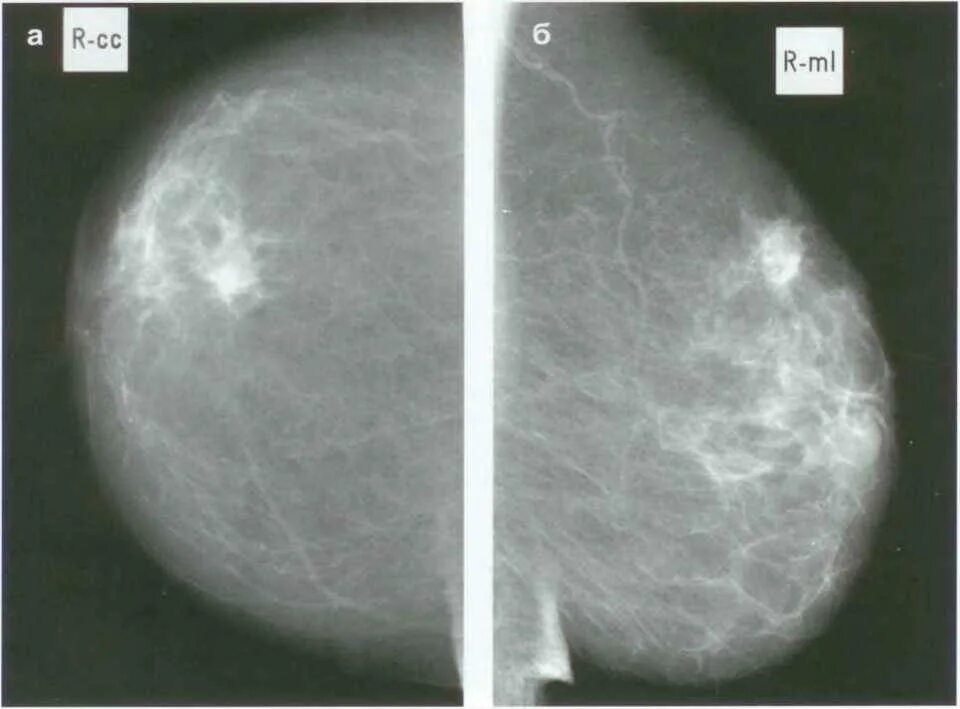

Что такое фиброаденоматоз молочных желез